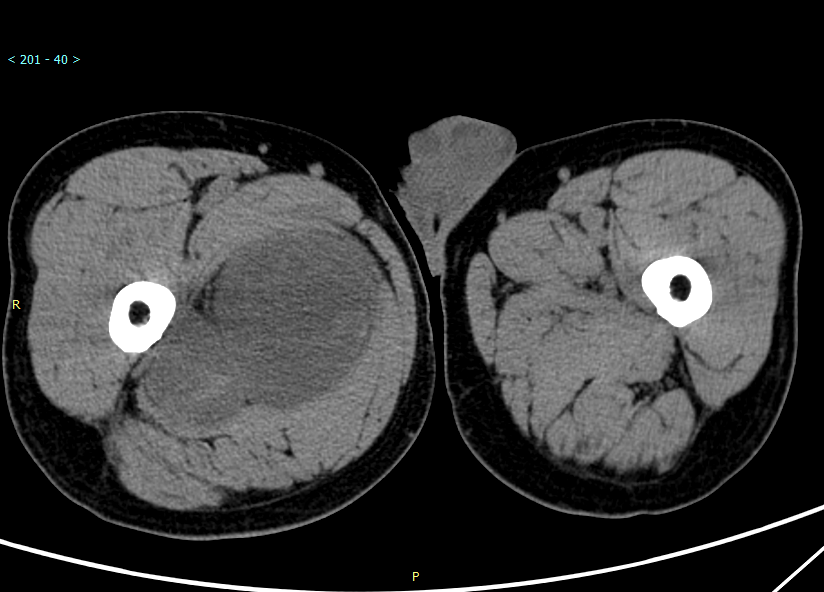

CT所见:右大腿上段内侧肌间隙见不规则肿块影,CT呈低密度影,增强扫描肿块实性部分及纤维分隔明显强化,呈蜂窝状。

CT: 显示与邻近肌肉相比等或低密度肿块,中心区域的密度低于周围,增强扫描实性成分可有轻到中度强化。这些表现与肿瘤的组织学结构相关,肿瘤周围大量的肿瘤细胞呈丝带状和轮辐状,而中央区域黏液基质丰富,肿瘤细胞较少,血管生成很少。CT 扫描对钙化的显示优于磁共振,肿瘤钙化可呈斑点或斑片状。

例 2 :X 线摄影表现为右股骨中下段周围见软组织肿块影,内见点状钙化,骨皮质毛糙,可见层状骨膜反应,髓腔内密度不均匀增高 ( 图 2a) 。CT 显示右股骨中下段周围见不规则软组织肿块,包绕右股骨生长,右股骨中下段骨质密度不均匀,见多发筛孔状骨质破坏区( 图 2b) ,增强扫描病灶实性成分不均匀轻度强化,内见多发血管影及斑片状无强化区( 图 2c) 。MRI 表现为不规则软组织肿块包饶右股骨中下段,T1WI 呈等信号,T2WI 及 STIR 呈高信号,内见多发低信号间隔( 图 2e,2f) ,右股骨中下段骨质信号异常,T1WI 低信号,T2WI 及 STIR 高信号。